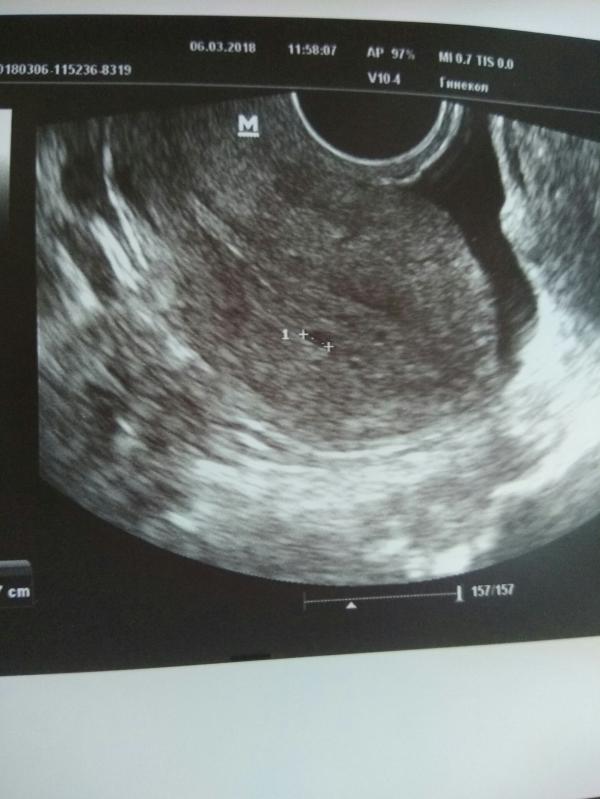

После падения ХГЧ и отмены дюфа прошло три дня, месячные не начинались, сегодня сходила на УЗИ. Нашли крохотное плодное яйцо, эндометрий совсем тонкий, матка не увеличена. К вечеру началась мазня.. Врач назначил доп анализы и прием Утрожестан во второй фазе. Надеюсь на лучшее)

@margaritavalova в четверг ХГЧ было 44, в субботу 30. Лаборатория одна и та же. Жёлтого тела уже нет, эндометрий 8 мм. И прогика своего нет.. два мм на картинке.

@vvvmashavvv да, такое бывает... Но мне ещё на первом УЗИ сказали, что картина не очень.. потом кровь, потом вот ещё УЗИ.. тем более срок крошечный, неделя задержки всего

Знаете что меня тут смущает..... вообще то плодное яйцо в матке видно после хгч не менее 1000. Ну 800....

@vvvmashavvv да ничего, я уже смирилась. Да, это действительно плодное яйцо, но увы, развиваться перестало ещё дня 4 назад. ХГЧ стал падать, отменила поддержку. Иду в новый цикл)